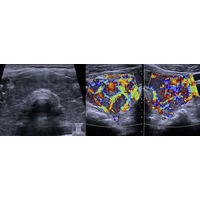

Abbildung 1: Sonografie der Schilddrüse bei Morbus Basedow, die untere Abbildung zeigt die vermehrte Durchblutung mittels Dopplersonografie

Abbildung 2: Magnetresonanztomografie eines Hypophysenadenoms (Quelle: Deutsche Gesellschaft für Endokrinologie).